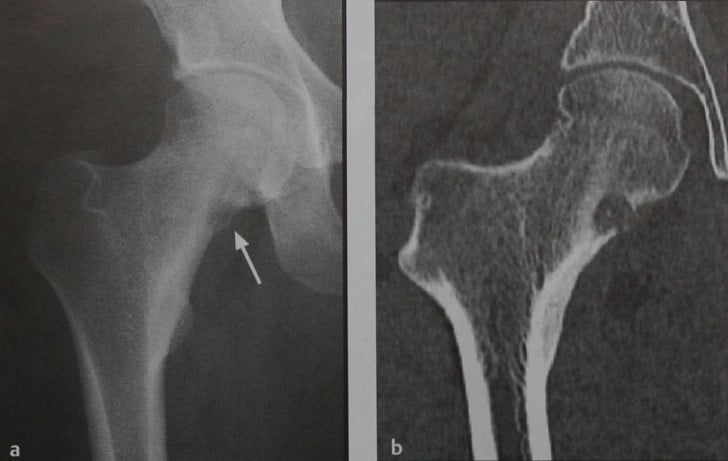

Рентгеновские снимки доброкачественных опухолей костей